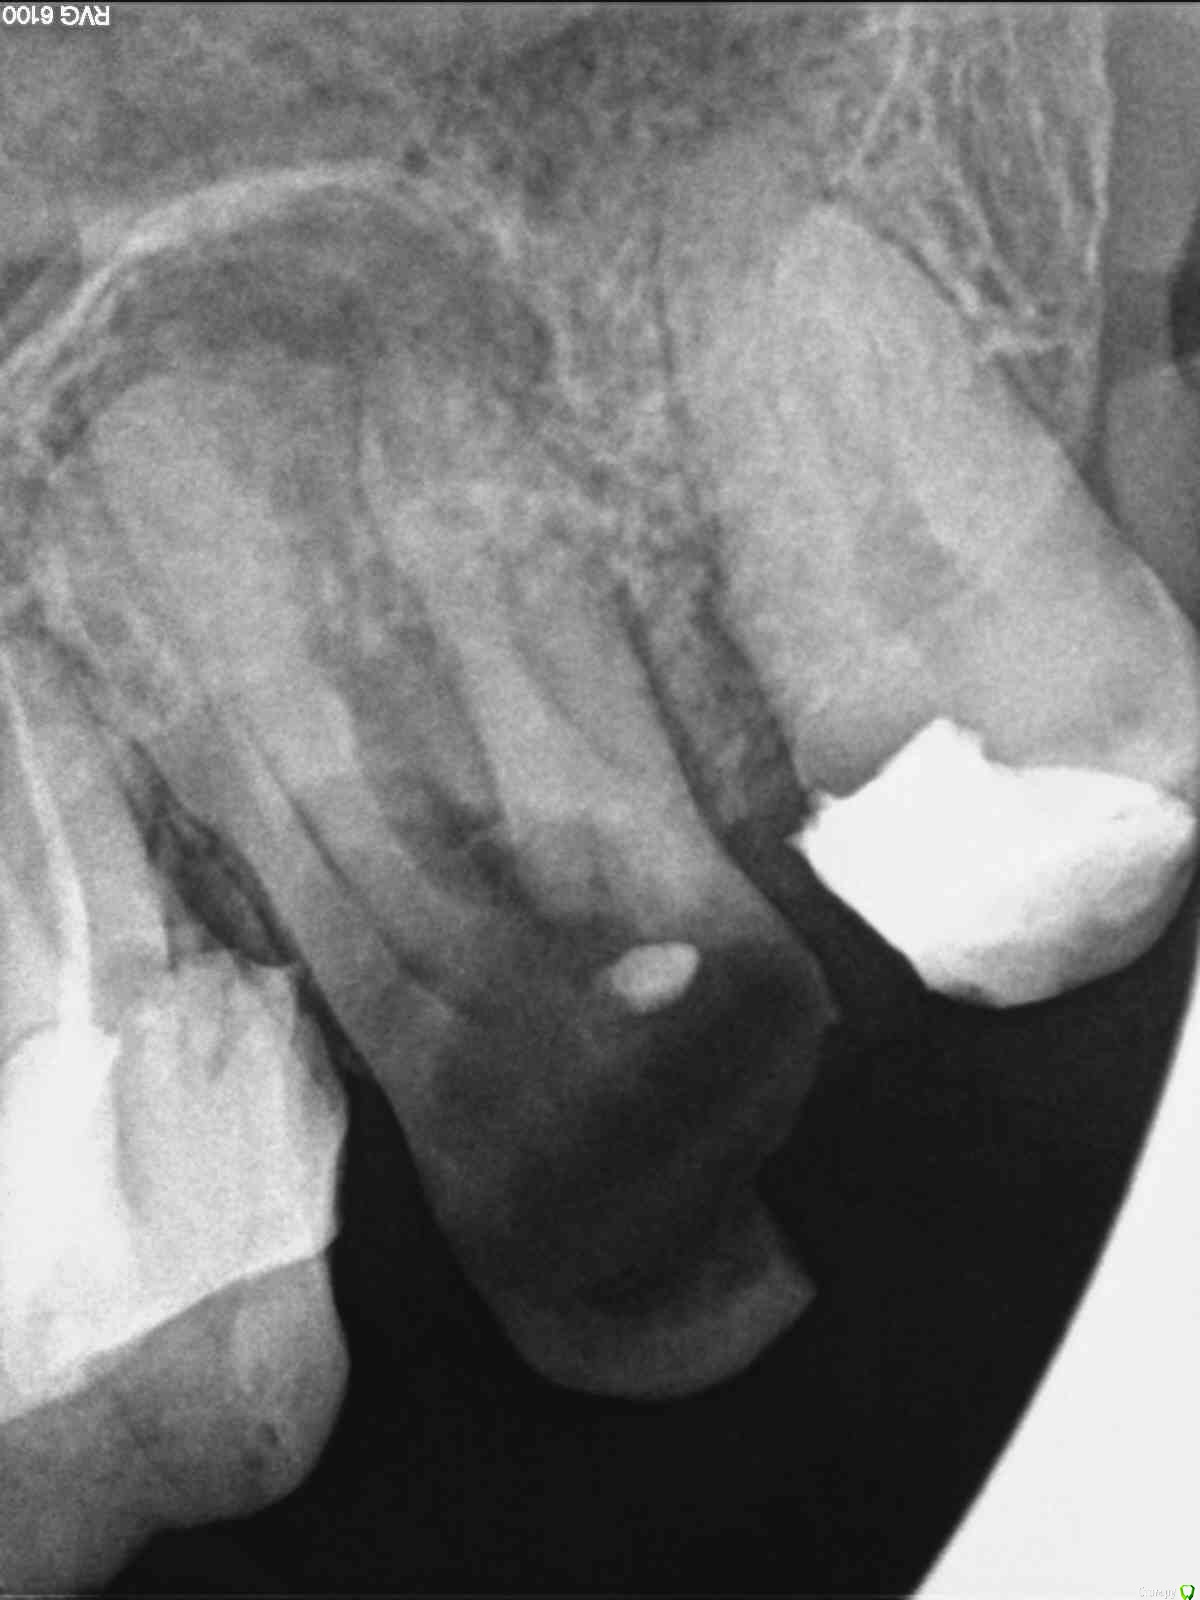

Ладонина Опубликовано 12 декабря, 2017 Поделиться Опубликовано 12 декабря, 2017 (изменено) Здравствуйте, зубы 1.6 и 3.6 в результате плохого лечения имеют кисты больших размеров. На деснах появились свищи. Киста верхнего зуба находиться в верхнечелюстной пазухе. Как быть и что делать? Удалять не хочу, только лечить или удалить кисты без удаления зубов.Зубы не болят.Scan.1.pdf Изменено 12 декабря, 2017 пользователем Ладонина 1 Ссылка на комментарий